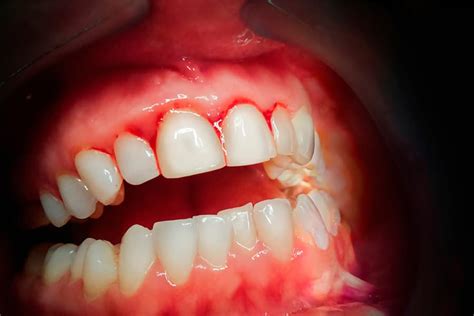

El sangrado de las encías se refiere a la presencia de sangre al cepillarse los dientes o al usar hilo dental. Las encías sanas deben ser firmes, de color rosa pálido y no deben sangrar fácilmente.

- Gingivitis: En la mayoría de los casos, el sangrado de las encías se debe a una gingivitis o a una lesión en la boca. Las encías están rojas, hinchadas y sensibles a la presión. Especialmente por la mañana o por la noche, al cepillarse los dientes o al utilizar el hilo dental, puede empezar a sangrar rápidamente en la zona inflamada. Esto se debe a que el cuerpo bombea automáticamente más sangre a las encías cuando se produce una inflamación, para poder eliminar más rápidamente las bacterias responsables de la inflamación.